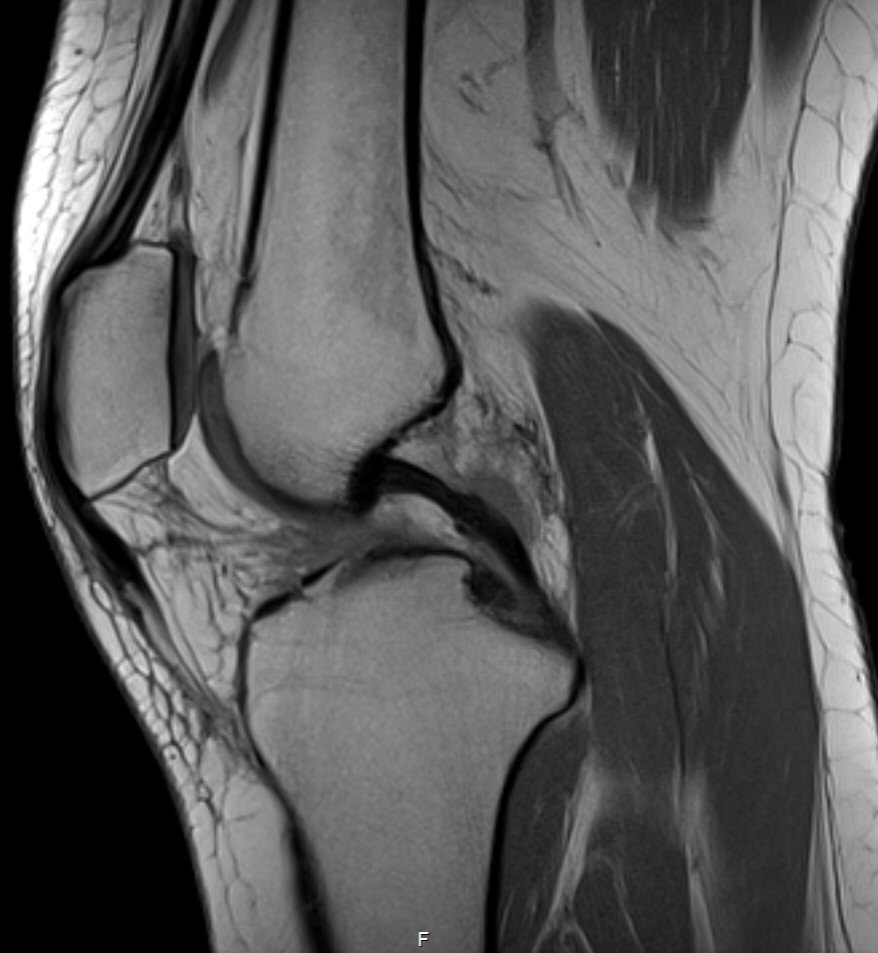

Det är bra att ha en rutin för hur man läser röntgenbilder generellt, även för MR-bilder. Ett exempel för knä kan vara så här:

Identifiera vilket som är lateralt (där man ser fibula). Börja laterala och gå mot medialt

Bläddra från ventralt till dorsalt, tillbaka till ventralt, upprepa vid behov.

Superiort till inferiort